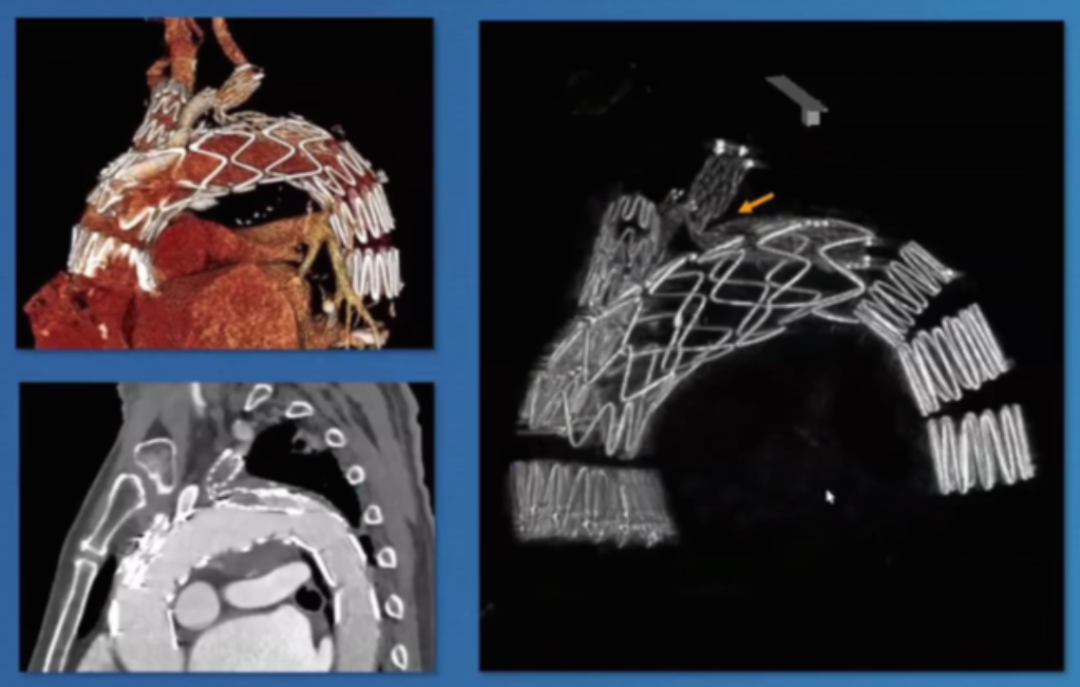

香港玛丽医院分享了38例主动脉弓分支支架植入病例的经验,其中28例为A/Br型,8例为B/Br型,1例为L型,患者平均年龄75.5岁,男性34例。30天死亡率为7.8%,手术中风率10.5%(2例严重+2例轻微),再干预率21%,逆行夹层3例,动脉瘤相关死亡2例。

此外,报告强调了健康主动脉的重要性,升主动脉直径<38mm是关键标准。曾有案例显示,在40mm主动脉植入支架后发生灾难性逆行A型夹层,这警示临床医生必须在健康主动脉段锚定,避免在夹层病理区域进行操作。

在主动脉介入治疗领域,支架设计持续创新。Terumo双分支支架采用大型矩形凹槽设计,即便旋转90度,仍能顺利接入分支,对于弓部曲线较为紧张的情况适配性更强。不过,该支架也面临技术挑战,手术中需要精准控制支架的旋转与对齐,以确保治疗效果。